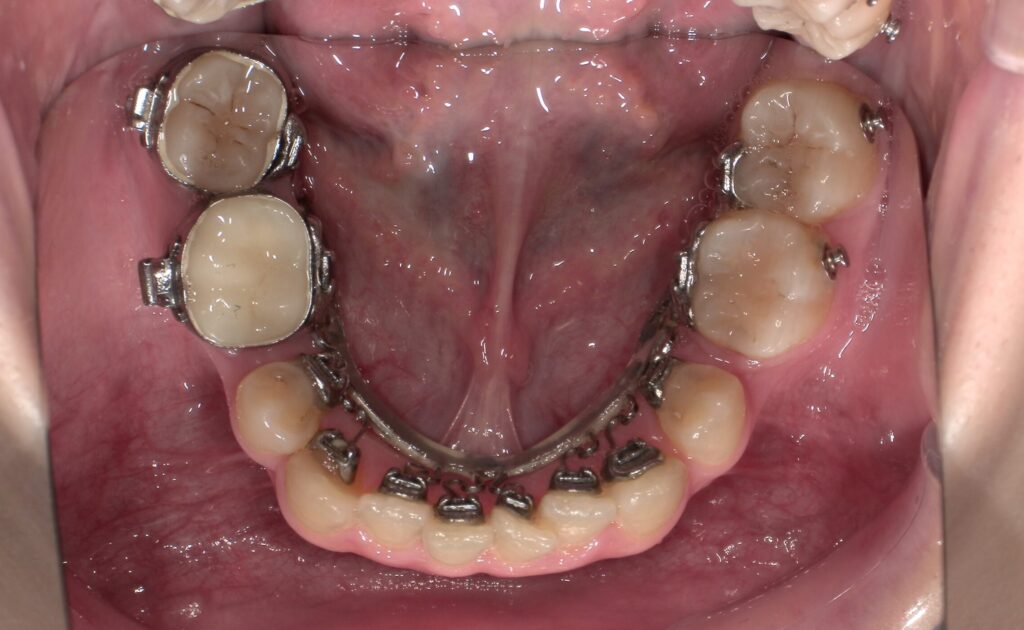

📸治療経過写真

当院で裏側矯正治療しているスタッフの経過写真をご参考にしてください。

上下左右小臼歯を1本ずつ計4本抜歯して現在も治療中です。「歯を抜いた隙間が閉じた量」、「前歯の移動量」、「正面から見た前歯の位置」に注目して見てもらえると、歯の移動の早さが目に見えて分かるかと思います。

初回装着時

下顎